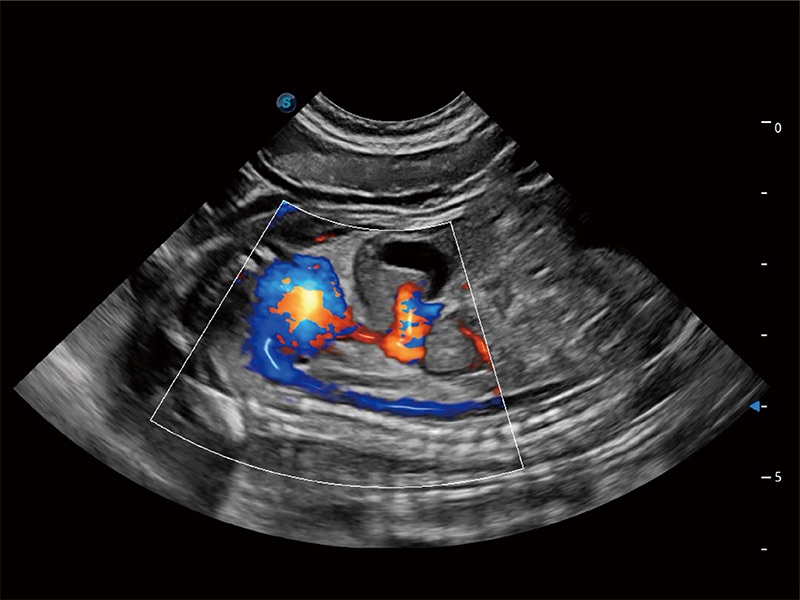

(犬)胎儿主动脉弓立体血流

(犬)二腔心血流